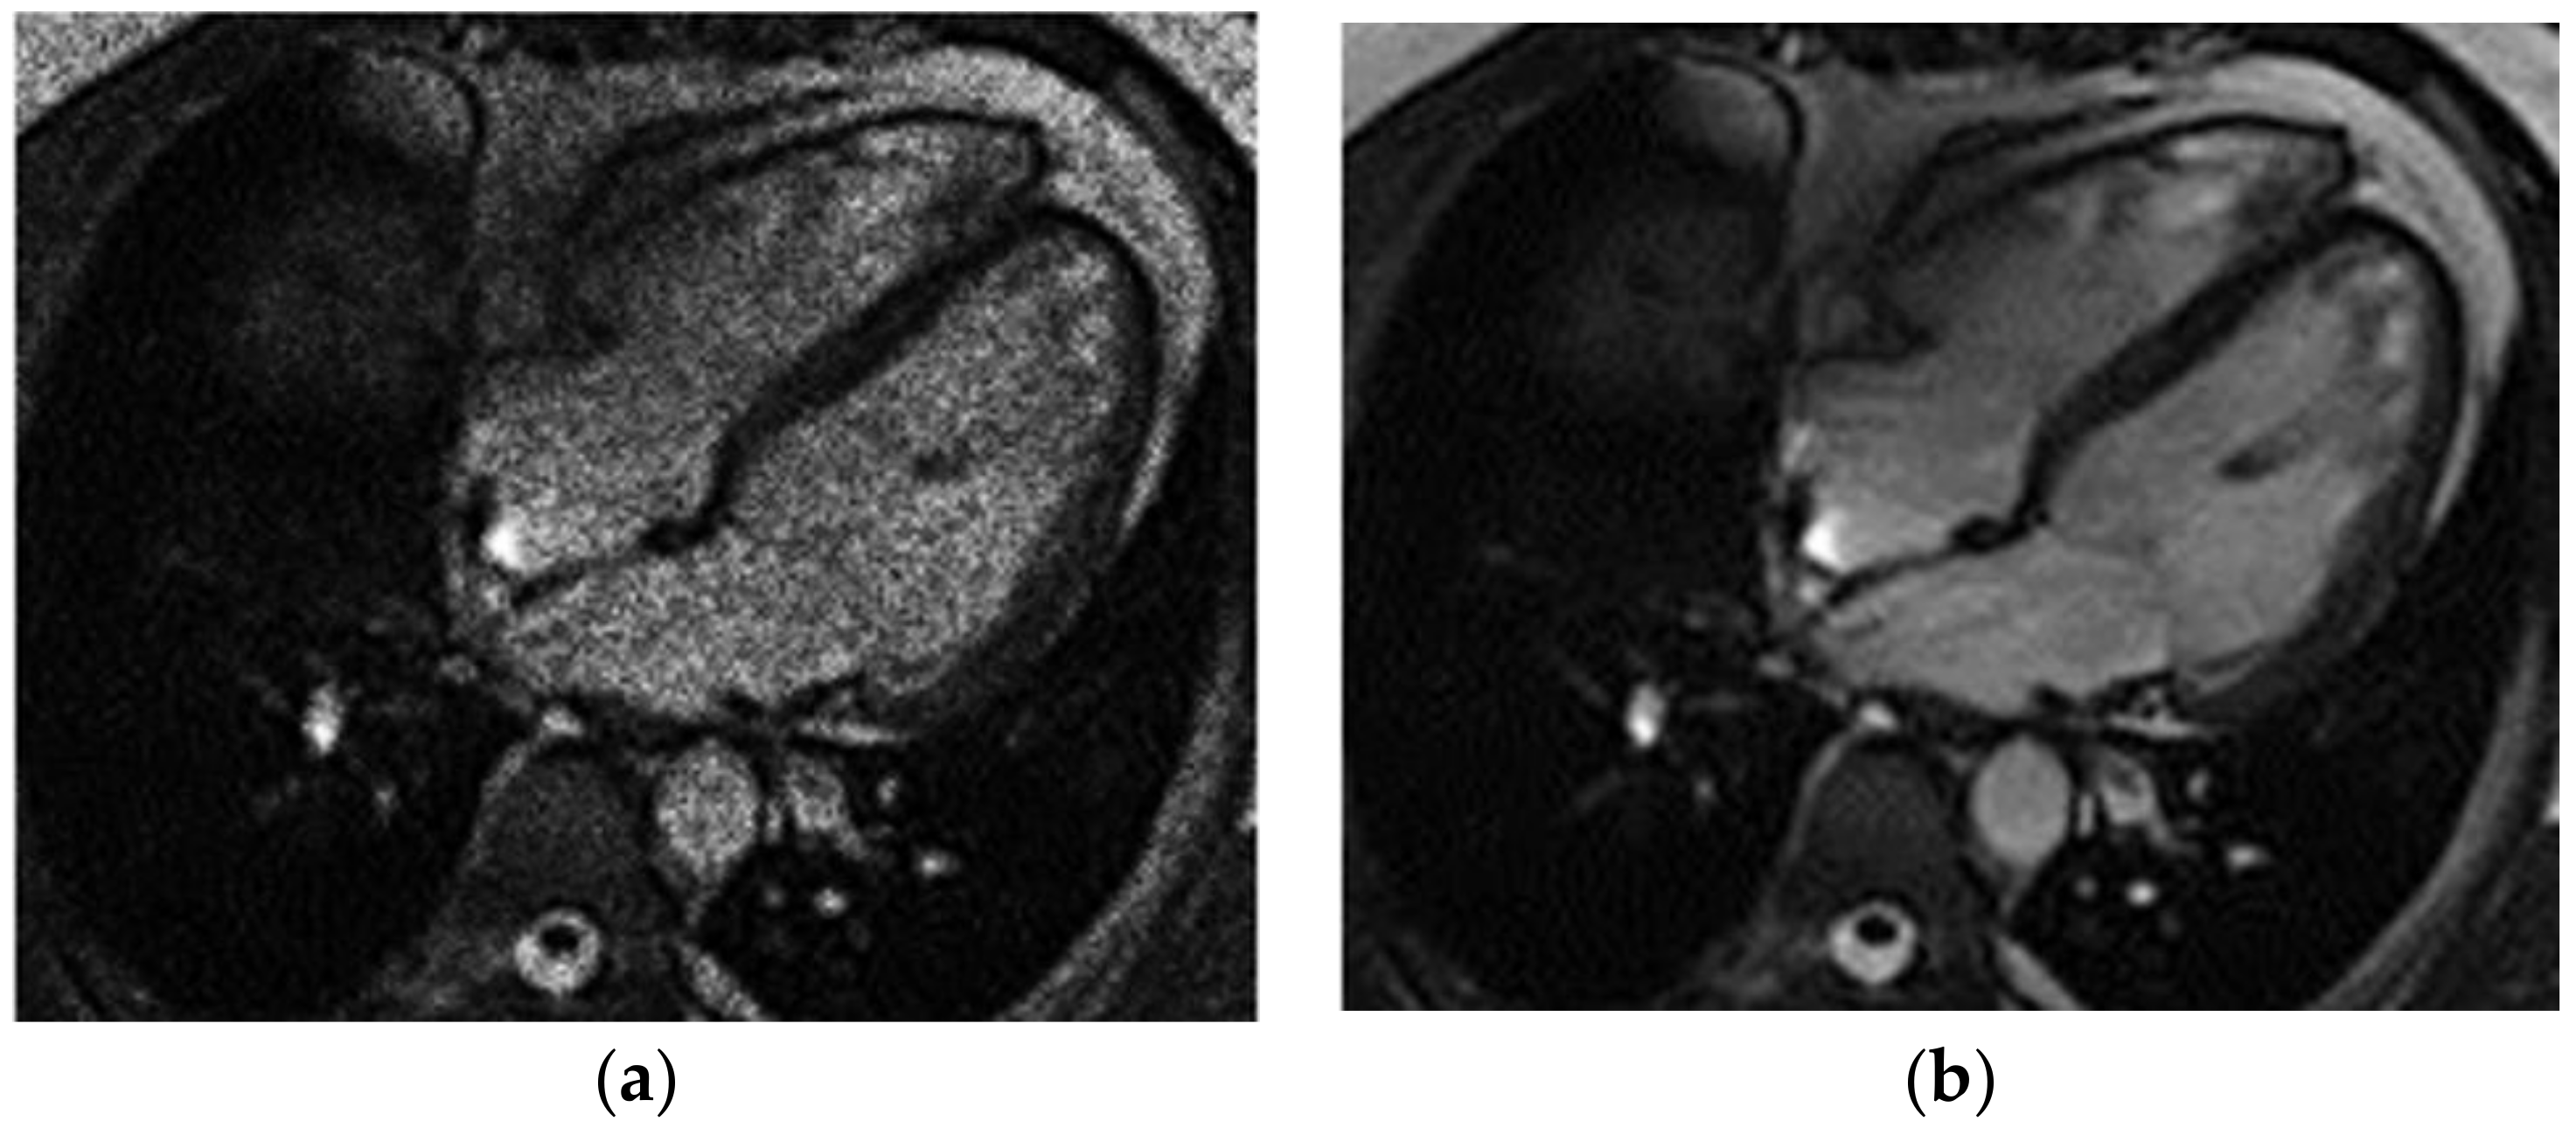

The application of this filtration model to an MRI image of the heart eliminates impulse noise as well as the geometric and fluctuation noise of the system (Figure 2).

Gaussian noise was added to the original MRI image in order to study the effectiveness of applying the model to eliminate mixed noise (Figure 2). The Gaussian noise was a simulation of the random noise in an MRI image in the DICOM format after a real biological object was scanned. It is assumed that the random noise in an MRI image of the heart is due to impulse noise and the geometric and fluctuation interference of the scanning system.

Figure 2. Heart MRI: (a) image with white noise and (b) denoised image.